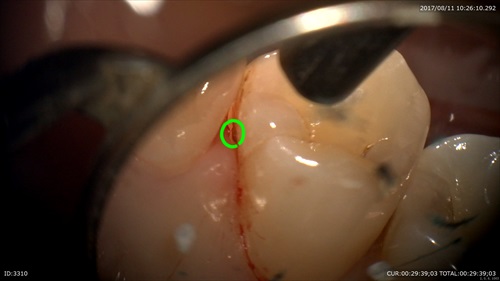

歯石発見!!

丁寧にデブライドメント

そしてレーザー